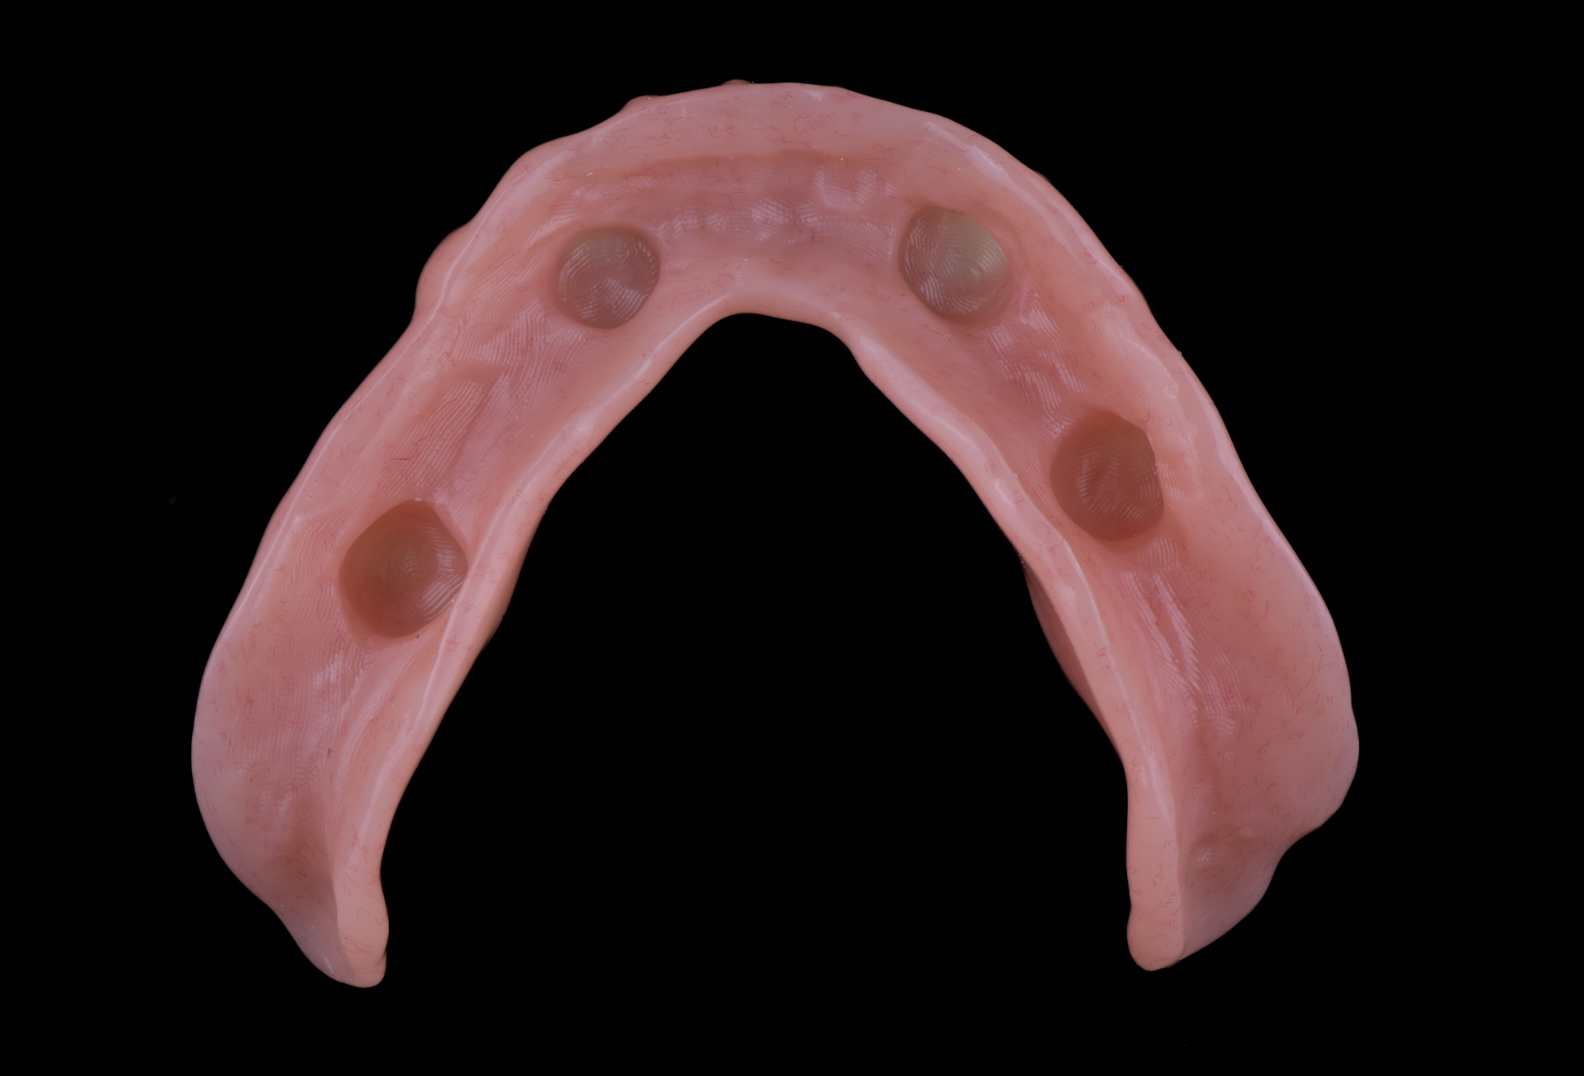

治療後

本症例では、下顎にインプラントを4本埋入し、そのインプラントを利用して入れ歯の安定性を高める計画としました。固定式のAll-on-4と比較し、清掃性、取り外しのしやすさ、費用面、将来的なメンテナンス性を総合的に考え、インプラントオーバーデンチャーが適していると判断しました。

そこで本症例では、下顎にStraumannインプラントを4本埋入し、それを支えにして入れ歯を安定させるインプラントオーバーデンチャーを選択しました。オーバーデンチャーは取り外しが可能でありながら、通常の総入れ歯よりも安定性を得やすい治療方法です。清掃しやすく、修理や調整にも対応しやすいため、長期的に管理しやすいという利点があります。

設計上で重視したのは、単にインプラントを入れることではなく、「どの位置で入れ歯を支えるか」「噛んだときにどこへ力がかかるか」「患者様自身が清掃しやすいか」という点です。インプラントの位置が不適切だと、入れ歯の安定性が得られにくいだけでなく、アタッチメント部分に過度な負担がかかることがあります。

本症例では、4本のインプラントを用いることで、2本支持と比較して支えの分散を図り、入れ歯の回転や沈み込みを抑えやすい設計を目指しました。咬合接触は、特定の部位に力が集中しないように調整し、咀嚼時の安定性とメンテナンス性の両立を考慮しました。

手術では、下顎にStraumannインプラントを4本埋入しました。事前の診査により、骨造成を行わずに埋入可能と判断したため、GBRは行っていません。インプラント埋入位置は、最終的なオーバーデンチャーの安定性、清掃性、アタッチメントの維持力を考慮して決定しました。

治癒後、インプラントの安定を確認したうえで、オーバーデンチャーの製作へ進みました。最終義歯では、噛み合わせ、人工歯の位置、清掃性、着脱のしやすさを確認しながら調整を行いました。